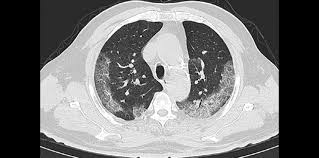

Can Ct Scan Detect Breast Cancer - Suburban Imaging Can A Ct Scan Detect Cancer : Early detection also helps doctors identify precancerous tissue abnormalities destined to become different types of scans for cancer include the following.. Staging and treatment of breast cancer. Apart from detecting cancers, the process is also used to diagnose various other diseases and is a lifesaving tool for doctors. During a breast mri , you lie on your stomach on a padded scanning table. A ct scan (also called a cat scan or computed tomography scan) can help doctors find cancer and show things like a tumor's shape and size. Ct scans can detect bone and joint problems, like complex bone fractures and tumors.

An mri scan of the breast may be. If you have a pet scan: Pet/ct scan combinations detect cancer in its earliest stages, when changes are happening at the cellular level. This combination scan is called a pet/ct. A ct scan of the heart may be ordered when various types of heart disease or abnormalities are suspected. In some cases, physicians use all three imaging techniques. This test may reveal whether breast cancer has spread to the bone. For example, ct has become a useful screening tool for detecting possible tumors or lesions within the abdomen. Learn how this test works, as well as its benefits and risks. It takes pictures from different angles. Why aren't pancreatic ct scans used in routine physical examinations to detect and prevent the spread of pancreatic cancer? A ct scan may be used to look for tumors in organs outside of the breast similar to a ct scan, a pet scan is a way to create pictures of organs and tissues inside the body. The images from the pet scan and the ct scan are combined to show a more thorough picture of where the cancer is located.

Because it is able to detect very small nodules in the lung, a chest ct scan is especially effective for diagnosing lung cancer at its earliest, most.

Can Pet Ct Replace Separate Diagnostic Ct For Cancer Imaging Optimizing Ct Protocols For Imaging Cancers Of The Chest And Abdomen Journal Of Nuclear Medicine from jnm.snmjournals.org If you have a pet scan: Bone scans, positron emission tomography (pet), and computed tomography (ct) all continue to be employed alone or in combination for the detection of breast cancers suspected to have spread. Doctors use this type of mammogram in women with breast cancer, but with. Computed tomography (ct or cat) scan. Each has its own strengths. The ct can detect some masses that would then need further evaluation. An mri scan of the breast may be. This lung cancer awareness month learn how future processing is able to detect lung cancer from ct scans with the help of ai.